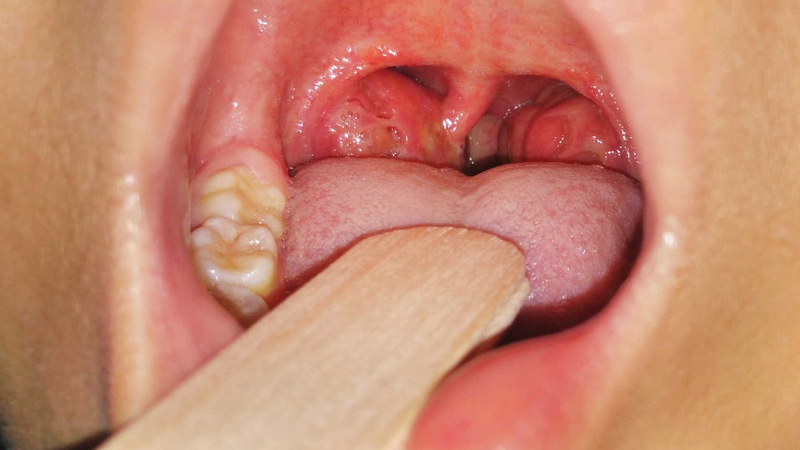

Amidan hay còn được gọi là amidan palatine là hai khối mô nằm đối xứng ở hai bên họng đóng vai trò quan trọng trong hệ miễn dịch, góp phần bảo vệ cơ thể chống lại các tác nhân gây bệnh xâm nhập qua đường miệng. Mỗi amidan có hình bầu dục, kích thước trung bình khoảng 2 đến 3 cm. Bề mặt amidan có nhiều nếp gấp tạo thành các hốc nhỏ là nơi chứa các tế bào miễn dịch.

Amidan là hai khối mô nằm ở hai bên họng, đóng vai trò quan trọng trong hệ miễn dịch. Tuy nhiên, amidan cũng là nơi dễ bị viêm nhiễm và khi tình trạng này diễn ra thường xuyên thì phẫu thuật cắt amidan có thể được xem là giải pháp tối ưu. Đối tượng phù hợp để cắt amidan là trẻ em từ 3 tuổi trở lên và người lớn mắc viêm amidan tái phát hoặc có biến chứng. Dưới đây là những trường hợp thường được bác sĩ chỉ định cắt amidan: